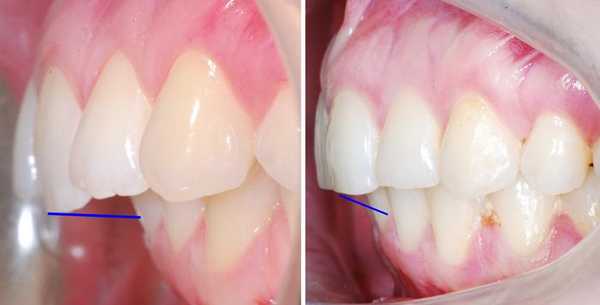

Из-за непропорционально выдвинутой верхней челюсти, дистальный прикус можно определить по выпуклому или «птичьему» профилю. Нос и верхняя губа выступают вперед, нижняя губа западает. Подборок скошенный, непропорционально маленький, иногда со складкой — «вторым подбородком». При серьезной дистальной окклюзии (с большой саггитальной щелью) губы в расслабленном состоянии не смыкаются и рот всегда немного приоткрыт.

Профиль до и после лечения дистального прикуса

Выпуклый профиль при дистальном прикусе